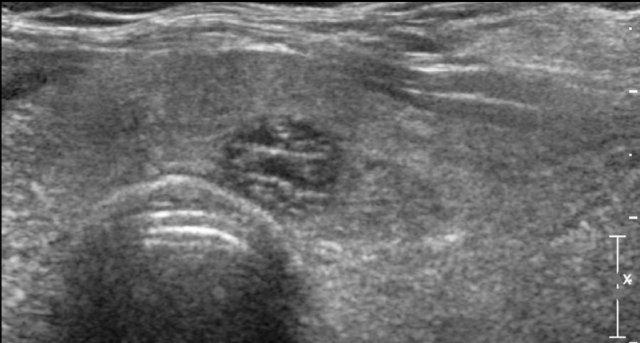

Spongiform nodules

Nốt dạng bọt biển có hình dạng giống miếng bọt biển, với ít nhất 50% thành phần cấu tạo bao gồm các thành phần nang nhỏ.

Không cần thêm đặc điểm mô tả siêu âm.